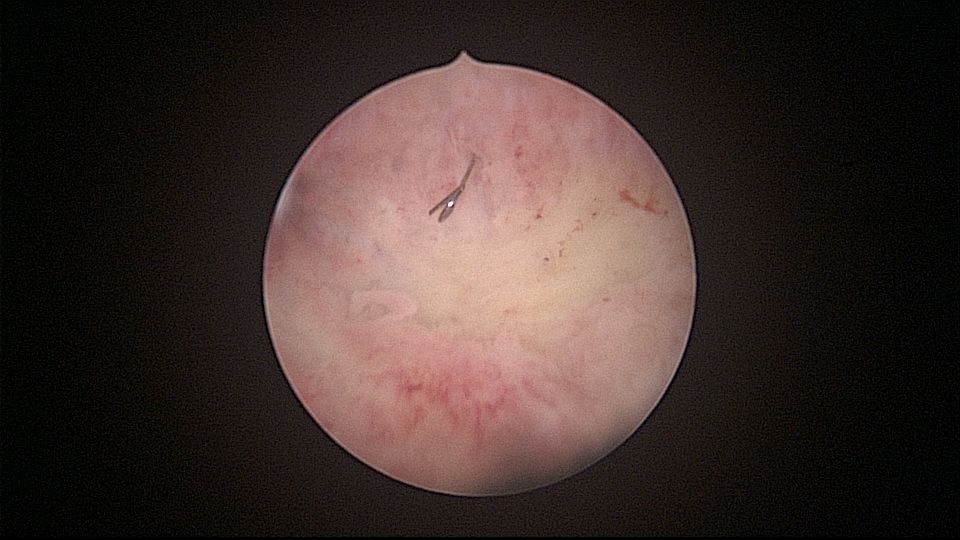

患者32岁,G6P2,顺产2次。2025年3月,停经56天,计划外妊娠,要求终止妊娠并放置节育环,考虑终止妊娠后宫腔大,担心环移位或脱落,要求固定节育环。γ环没有尾丝,用4号丝线连接环及不锈钢挂钩,将挂钩插入宫底肌层固定,异物钳原位固定曼月乐,退出宫腔镜,结束手术。术后患者未回院复查节育环位置。